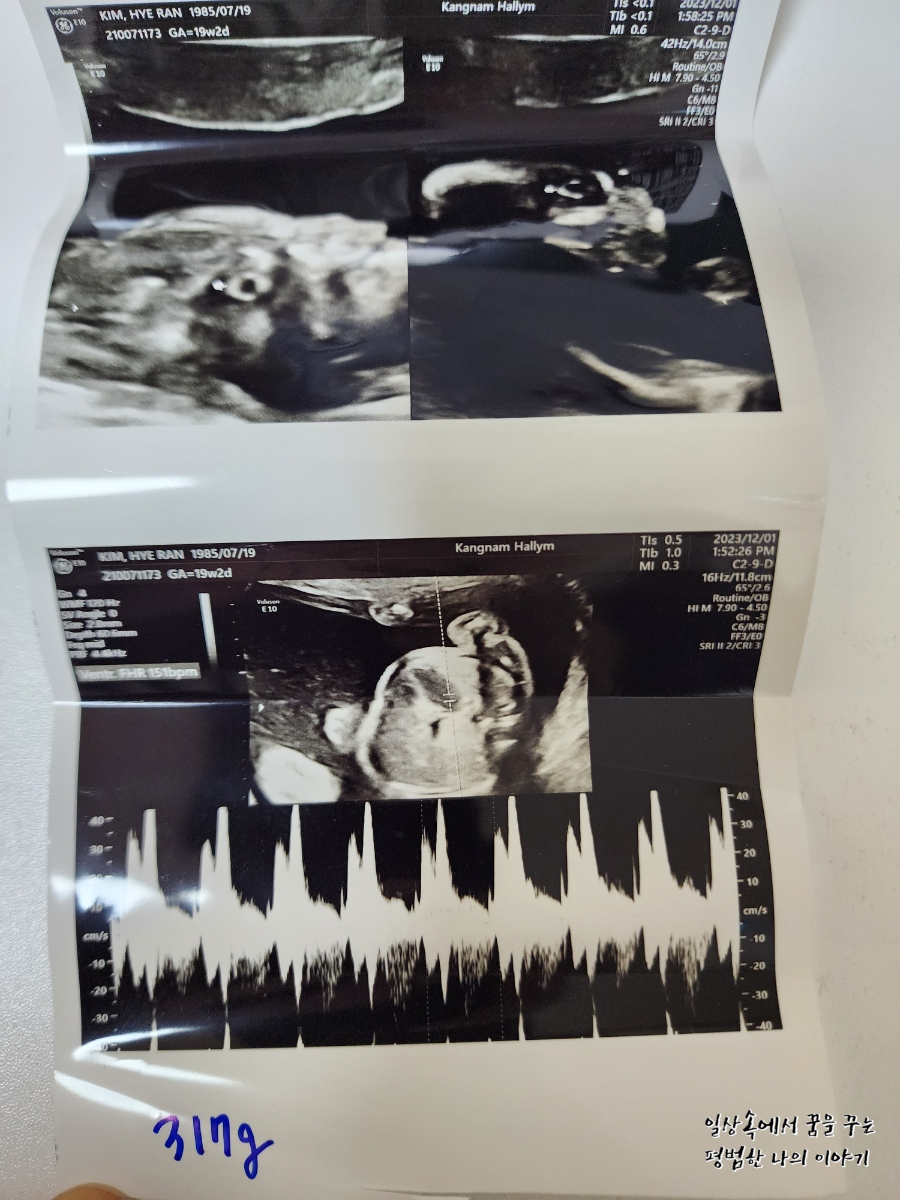

BPD(Biparietal Diameter, 위에서 볼 때 태아 머리 단면의 가장 긴 길이): 4.31cm

HC(Head Circumference, 태아 머리둘레): 16.12cm

AC(Abdominal Circumference, 배 둘레): 15.38cm

EDD(Expected Date of Delivery, 출산 예정일): 2024년 4월 24일

FL(Femur Length, 허벅지뼈 길이): 3.26cm

GA(Gestational Age, 임신 주차): 19주 차 2일

EFW(Estimated Fatal Weight, 태아 예상 체중)=EBW(Estimated Body Weight): 317g

Cereb(Cerebelleum, 소뇌 크기): 19.96mm

FHR(Fetal Heart Rate, 심장박동 수): 151bpm

CL(Cervical Length, 자궁경부 길이): 정상

AF(Amniotic Fluid, 양수): 정상